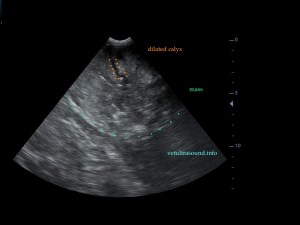

Findings: A mixed echotexture mass which was pushing the intestines caudally was found. The mass had decreased blood flow with the Color Flow Doppler. Diffuse calcinomatosis was also noted(pic1). This mass originated from the right kidney(pic3). Only near the renal pelvis there was a small area that resembled normal kidney tissue(pic2).

Ευρήματα: Βρέθηκε μάζα η οποία καταλάμβανε όλο το πρόσθιο τμήμα της κοιλιακής χώρας και απωθούσε τον πεπτικό σωλήνα προς τα κάτω και πίσω. Η μάζα είχε μειωμένη αιμάτωση στον έλεγχο με έγχρωμο Doppler ενώ το παρέγχυμά της ήταν συμπαγές με αφθονία επασβεστώσεων(pic1). Η μάζα αυτή αφορούσε το δεξιό νεφρό η οποία τον είχε αλλοιώσει τελείως (pic3)και μόνο στο τμήμα κοντά στην νεφρική πύελο διατηρούσε τη φυσιολογική δομή(pic2). Τα υπόλοιπα παρεγχυματικά όργανα βρέθηκαν φυσιολογικά. Δεν υπήρχε διάταση του σύστοιχου ουρητήρα και η ουροδόχος κύστη βρέθηκε φυσιολογική.